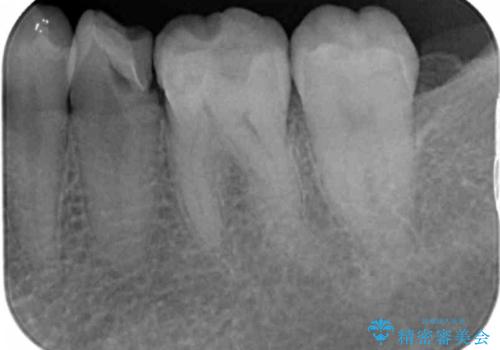

X線検査を行なったところ、以前他院にて治療した白い詰め物の下に虫歯の再発を認めました。

詰め物を除去したのち、虫歯を丁寧に除去することで神経を保存しながらセラミッククラウンによる補綴治療を行うことができました。

外から見て白くきれいな修復が為されていたとしても、内部で虫歯が再発していることは多々あります。

違和感を感じたら早期にX線検査を行い、神経が保存できるうちに治療を行うことが重要です。